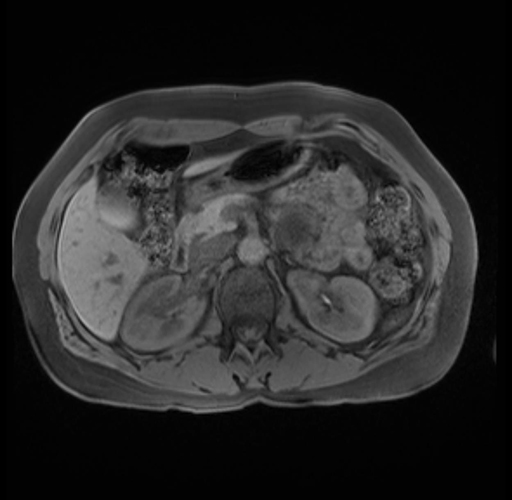

Imaging Analysis

Look through the patient's CT scan to identify any areas of concern for the necessary procedure.

Based on your CT findings, which issue(s) are present and would give reason for "planned slowing down moment(s)" in this case?